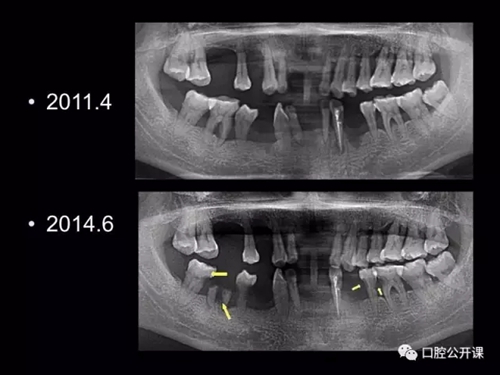

一例廣泛型侵襲性牙周炎5年臨床追蹤下

楊淑銀醫(yī)師用他的一例侵襲性牙周炎五年臨床病例追蹤來(lái)縮影一個(gè)青年牙周醫(yī)師的成長(zhǎng)之路,帶我們一起探索看似平凡枯燥的牙周基礎(chǔ)治療到底有怎樣的重要性?